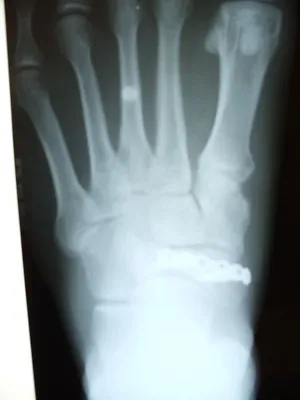

Below is a sequence of navicular fracture repair. An x-ray of a displaced navicular bone fracture (furthest left). Surgical repair inter-operative picture of placed plate with screw fixation to hold the fracture fragment in place and provide stability (center top). Lateral view of post-operative x-ray repair of fracture (center bottom). Anterior-Posterior x-ray of post-operative repair of navicular fracture with screws and surgical plate visible (furthest right).